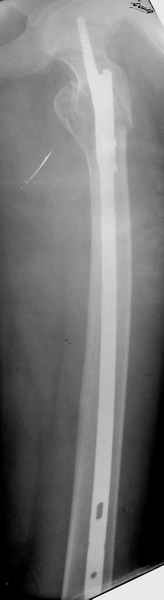

Спасибо за все ответы и комментарии по этому вопросу. Неделю назад мы прооперировали пациентку. Представляем ее снимки.